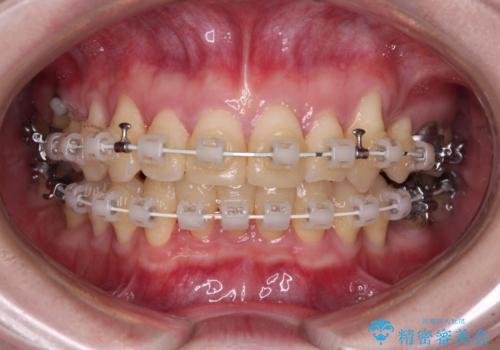

- 矯正装置

- 審美装置

- 八重歯と正中のズレを気にして来院された患者様です。

上顎左側が八重歯になっており、上顎正中が左側にずれていました。

上顎左側の第一小臼歯を抜歯し、補助装置を用いて正中位置を改善しながら八重歯を解消していくこととしました。

下顎前歯が1本欠損していたため、上下正中の位置が合わせるという目標はなく、鼻筋に上顎正中を合わせていくように移動を行いました。